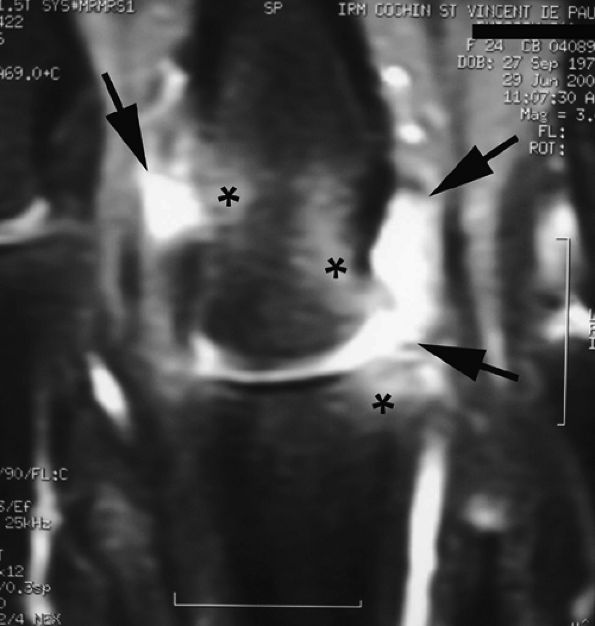

FIGURE 11.142 ● Osteoarthritis of the PIP joint on (A) a coronal proton density fat-suppressed image and (B) a sagittal post-contrast fat-suppressed T1-weighted image. Erosive osteoarthritis with foci of subchondral bone edema (asterisks), a bone cyst (arrowheads), and capsuloligamentous thickening (black arrows) are seen. A possible thin channel between the cyst and the joint (white arrow) or diffuse synovitis (small circles) may also be seen.